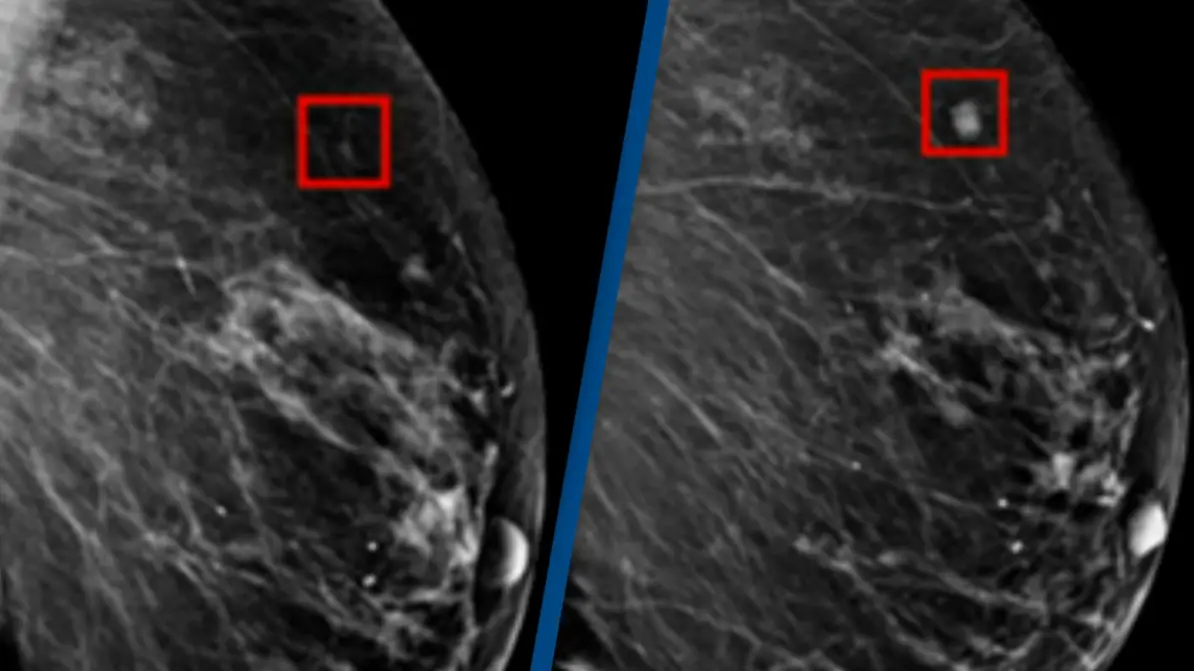

An AI program was successfully able to detect breast cancer in a woman four years before it developed.

AI is being used in cancer screening technology to pick up potential issues long before they develop into something harmful.

"This technology can look at mammograms and identify areas that a human radiologist may want to look at more carefully.

"What this work does is it identifies risk. It can tell a woman 'you're at high risk of developing breast cancer' before you develop breast cancer."